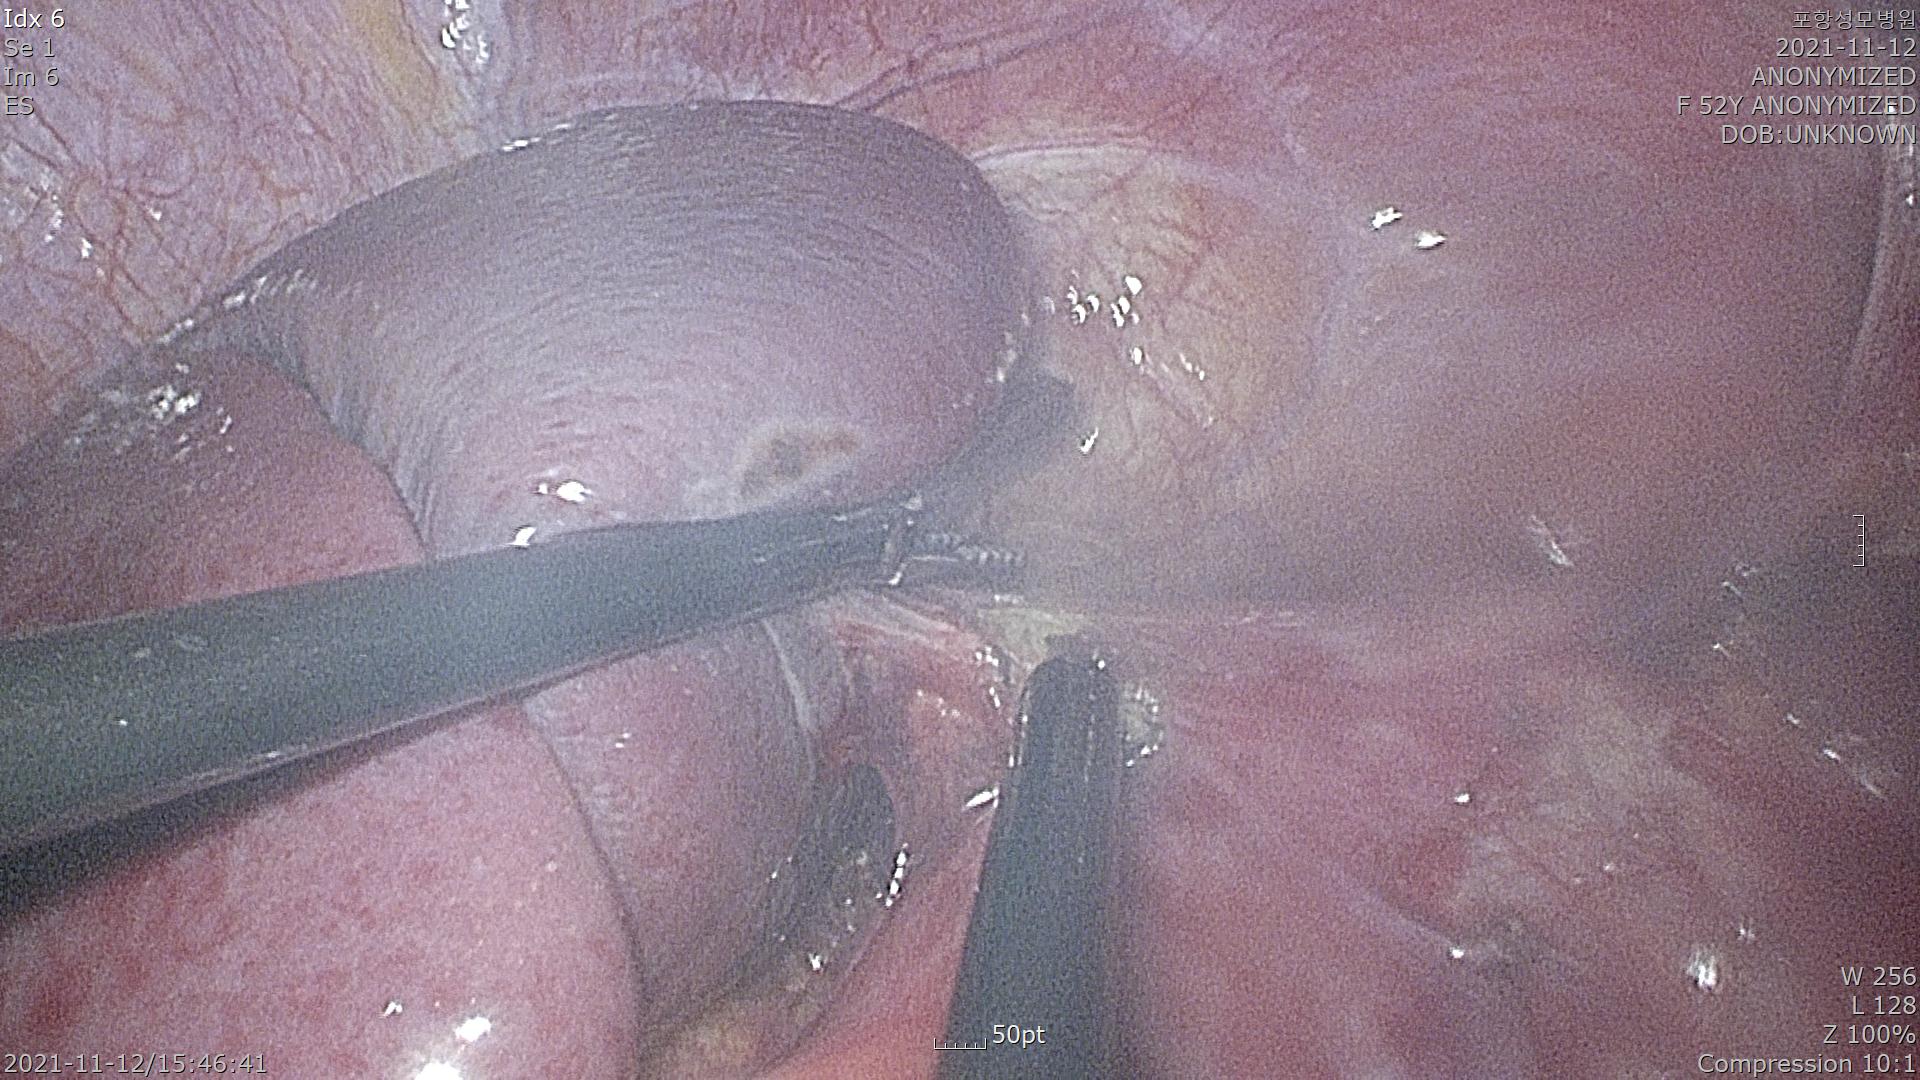

복강경 수술 시작했습니다.

부신은 후복강 기관에 있는 장기이기 때문에 복막을 열고 들어가야 확인됩니다.

위 사진에서 복막을 열고 있습니다.

좌측에 비장이 확인되고 비장에서 출혈이 심할 수 있기 때문에 조심스럽게 박리합니다.

낭종이 사이즈가 커서 흡인을 시행하고 들고 있는 모습입니다.

낭종을 공급하는 혈관을 클립으로 잡은 모습입니다.